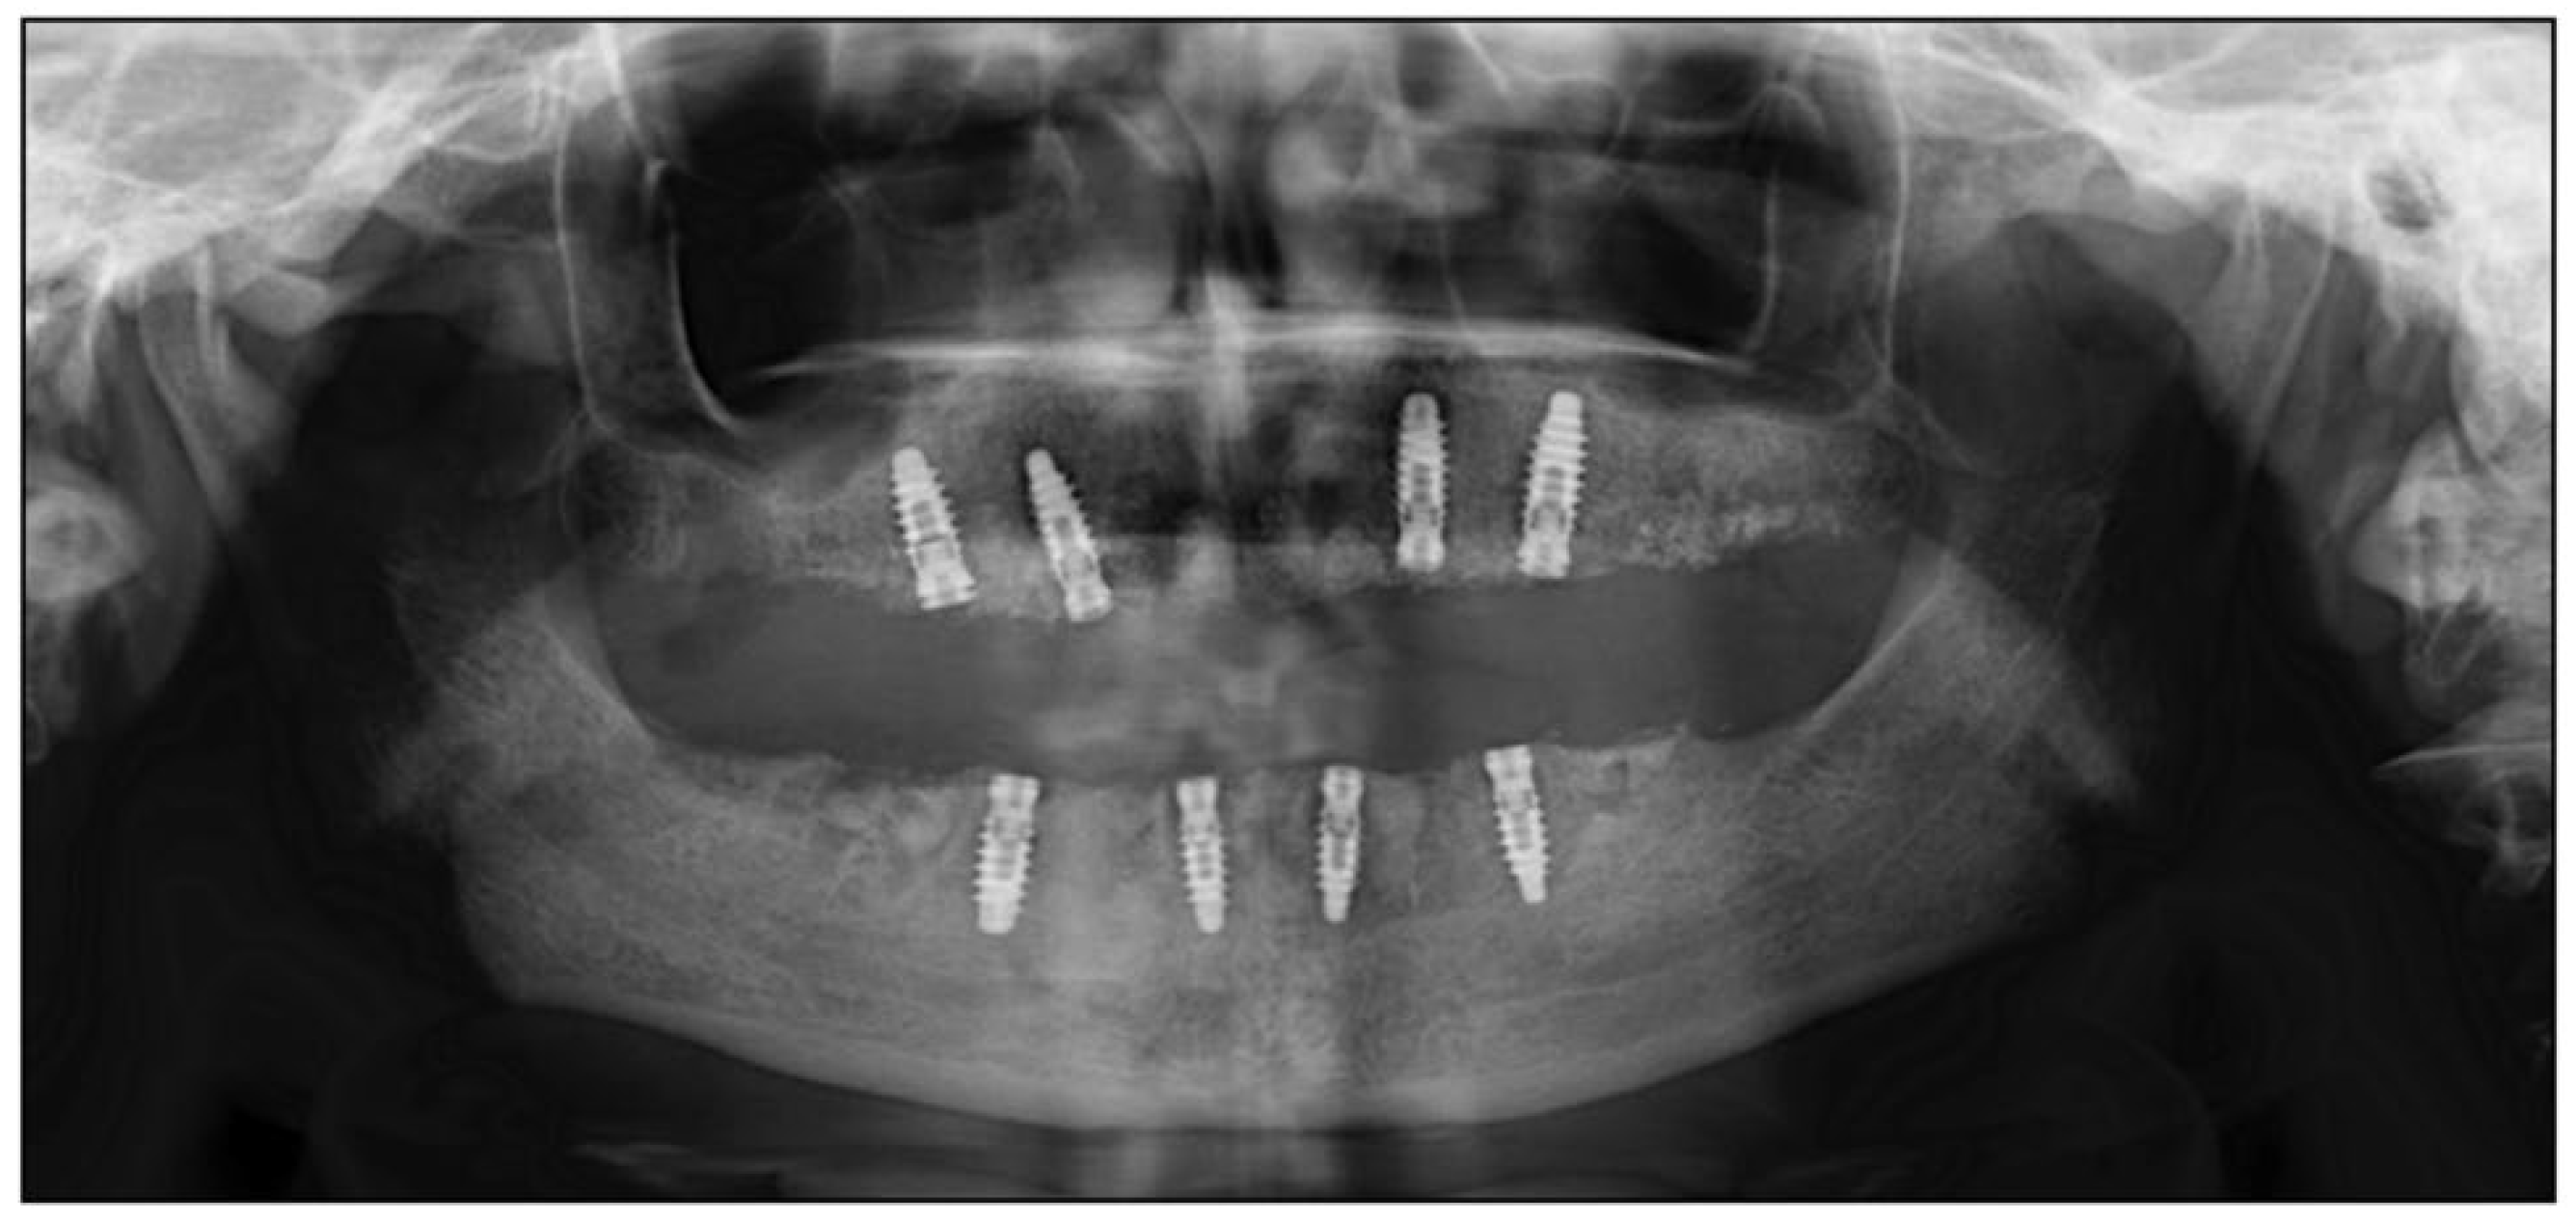

2. Case Report